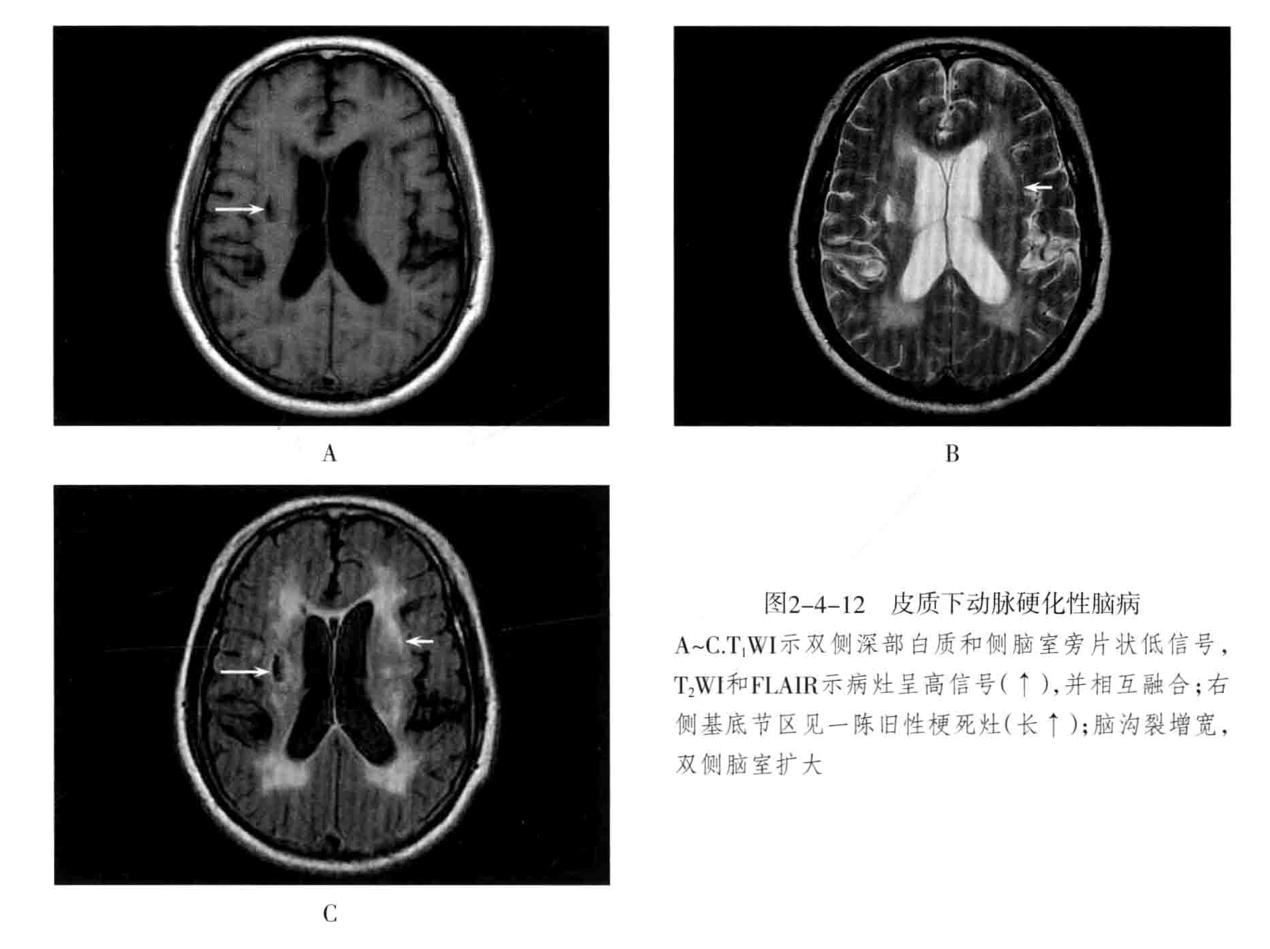

九、皮层下动脉硬化性疾病

又称为Binswanger病、进行性皮质下血管性脑病。为老年人在脑动脉硬化基础上的大脑半球白质弥漫性脱髓鞘性脑病。大多数发生在50岁以上。主要累及侧脑室周围、半卵圆中心等皮质下脑深部白质,多为双侧性,常伴有腔隙性脑梗死、脑萎缩。临床表现为进行性痴呆。病情可缓解,并反复加重。

- CT平扫表现为侧脑室周围及半卵圆中心脑白质可见斑片状低密度影,以侧脑室前角、后角周围最为明显,严重者大脑各叶白质全部明显累及,双侧对称性分布。可伴有不同程度脑萎缩,常合并基底节区、丘脑区多发性腔隙性梗死灶。

- MRI表现为中央半卵圆区及双侧侧脑室旁,尤以前角附近明显,侧脑室周围病灶常融合成不规则带状,且双侧比较对称。T1WI低信号,T2WI高信号,无占位效应。